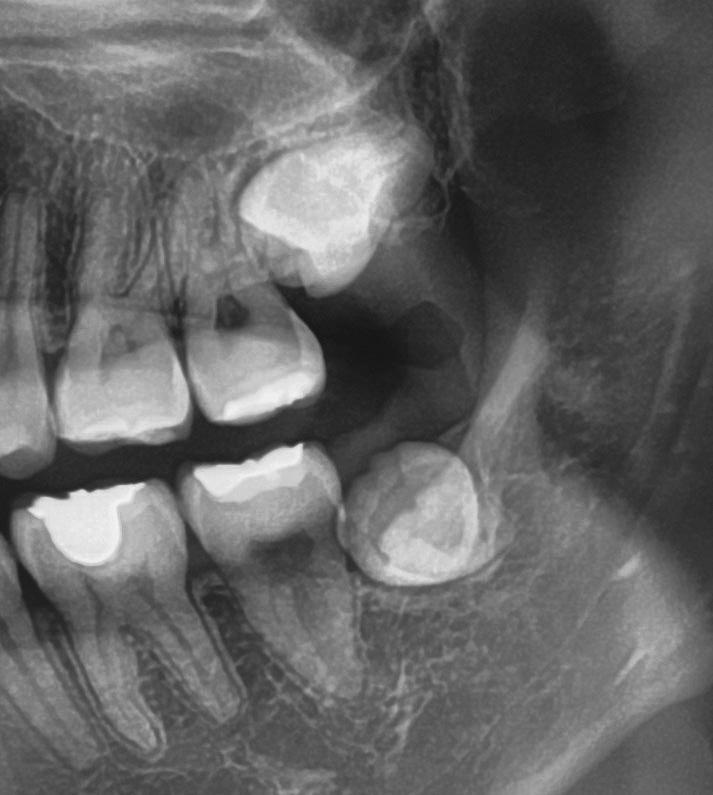

Il seguente caso chirurgico è di un 4.8 mesio-inclinato e parzialmente incluso. Dopo un’incisione a busta, il

dente è stato separato al centro per fare una coronectomia, prima della porzione distale e successivamente della porzione mesiale. Facendo leva quindi è stato possibile rimuovere le radici unite. Figg. 165-172

Figg. 165-172 - Caso 3: tecnica di estrazione con divisione orizzontale utilizzando il manipolo dritto. Fig. 165 Fig. 166 Fig. 167 Fig. 168 Fig. 169 Fig. 170 Fig. 171 Fig. 172

Dalla radiografia (Fig. 166) sembrava che il dente avesse due radici separate, quindi è stato eseguito un taglio orizzontale utilizzando il manipolo dritto per sezionare il dente a metà. Tuttavia, la corona si è frat-

turata poiché in realtà le radici erano unite e il dente non è stato sezionato completamente.

Bisogna prendere in considerazione sempre molti fattori come, ad esempio, la forma delle radici, il sottosquadro nella regione distale del secondo molare e l’osso alveolare disto-vestibolare. Se necessario la corona e le radici vengono separate intenzionalmente per estrarre il dente, proprio come in questo caso.